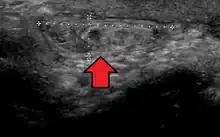

No diagnóstico de hérnias abdominais, a imagem é o principal meio de detectar hérnias diafragmáticas internas e outras hérnias não palpáveis ou não suspeitas. A tomografia computadorizada com múltiplos detectores (TCMD) pode mostrar com precisão o local anatômico do saco de hérnia, o conteúdo do saco e quaisquer complicações. A TCMD também oferece detalhes claros da parede abdominal, permitindo que as hérnias sejam identificadas com precisão.[9]